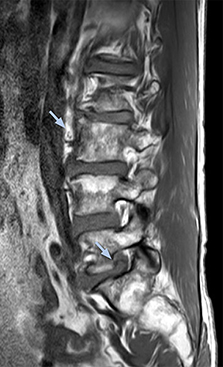

“For example, in sagittal images, when the presence of fat is observed in the intervertebral foramen, it suggests that there is a margin around the nerve. Similarly, the absence of fat indicates that the nerve is being compressed. So, we used to deduce nerve compression indirectly. With NerveVIEW, however, we can observe the condition of the nerves directly, regardless of the presence or absence of fat. We always prefer such direct observation of anatomy over having to make an inference about it.”

“Although symptoms of typical disc herniation and atypical hernia are very similar, the actual site of herniation is different. It is therefore important to characterize the nerve’s condition both inside and outside of the intervertebral foramina. “Conversely, if we see no abnormality in NerveVIEW, we can assume at least that there is no severe condition that requires surgery. Like this, it can help us avoid unnecessary surgery. NerveVIEW can have a tremendous impact in this way.”

“NerveVIEW is really useful for those cases where a nerve disorder is strongly suspected based on the clinical examination but our regular MRI images do not show any findings. These atypical herniations and spinal canal stenosis, occurring in 5% to 15% of the total lumbar herniation/stenosis cases are our main target when using NerveVIEW,” says Dr. Yabuki.